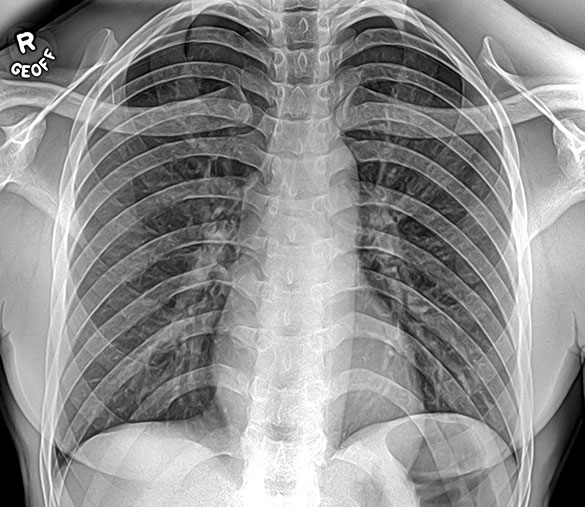

An x-ray (radiograph) is a quick, painless medical test that helps physicians diagnose and treat medical conditions. Radiography involves exposing a part of the body to a small dose of ionizing radiation to produce pictures of the inside of the body. X-rays are the oldest and most frequently used form of medical imaging. They are often used to help diagnose fractures in bones, or infection, injury or locating a foreign object in soft tissue. Diļ¬erent parts of the body absorb the x-rays in varying degrees. Dense bone absorbs much of the radiation while soft tissue, such as muscle, fat and organs, allow more of the x-rays to pass through them. As a result, bones appear white on the x-ray, soft tissue shows up in shades of gray and air appears black.

Getting an X-Ray (Radiograph) involves exposing a part of the body to a small dose of ionizing radiation to produce pictures of the inside of the body. X-rays, or radiation like light or radio waves, pass through most objects, including the body. Once the X-Ray machine is carefully aimed at the part of the body being examined, the x-ray machine produces a small burst of radiation that passes through the body, recording an image digitally.

Generally, two or three X-rays will be taken depending on the body part that is being viewed. You will be asked to remain as still as possible during the very short exposure time. If necessary, you will be instructed to hold your breath in order to prevent motion from blurring the images.